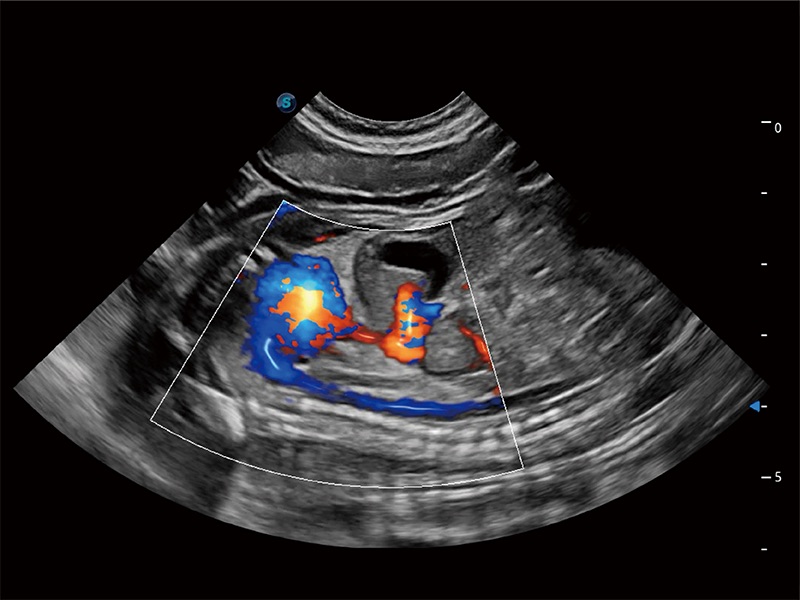

极大提升超低速微细血流的检出能力,同时更精准地滤除软组织和超声信号,为兽用医生提供以往无法通过常规血流获得的疾病诊断信息。

在传统二维血流成像的基础上,呈现血流的立体感,具有动感的生命力之美。即便是微小的血管也能轻松应对,提高了血流的视觉敏感性。

ProPet 80 配备了丰富的心脏探头群、先进的成像技术和专业的心脏测量工具,可帮助动物医生为不同体型和生理结构的动物提供心脏和心肌功能的全面评估。

实时用颜色表示心肌组织运动,观察和定量组织的运动情況,对快速检测与评估心肌的灌注和活性、电传导及心肌收缩和舒张功能等均能提供重要的诊断信息。